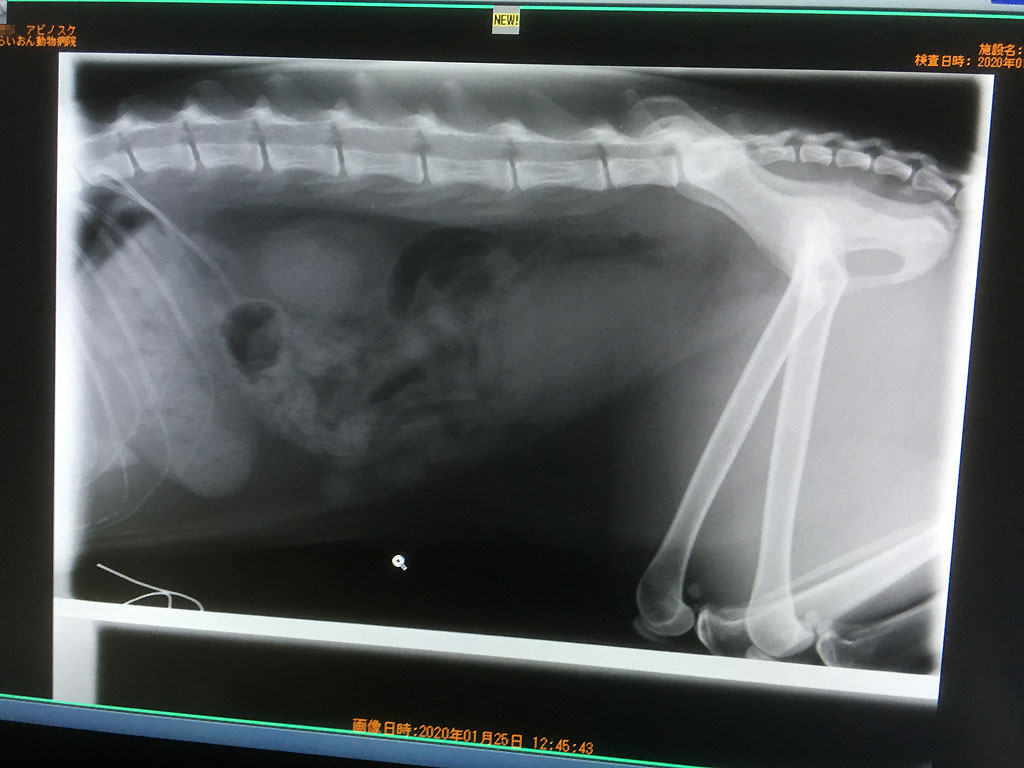

そして、念の為、石が詰まってないかレントゲンを勧められたので、こちらからもして欲しかった位なので、すぐにお願いしました。

まずは横からのレントゲン。

レントゲンを見てもいつもよく分からないのですが、先生のご説明によると、取り敢えず、石は詰まってないとの事、そして、尿も膀胱にパンパンに溜まっている程ではないとの事。

とにかく、石が詰まって尿が出ず、急性の腎不全に陥って死んでしまうという事はなさそうだったので、本当に安心したぞ、アビのすけ君。